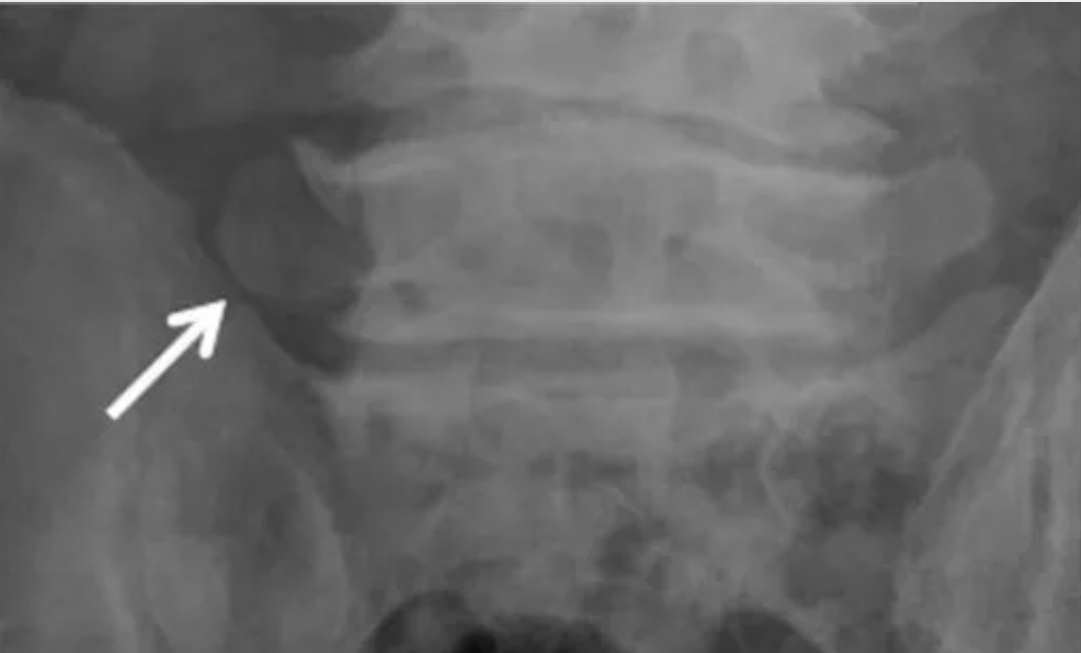

I型:横突发育不良增大,冠状位高度>19mm,尚未形成假性关节面